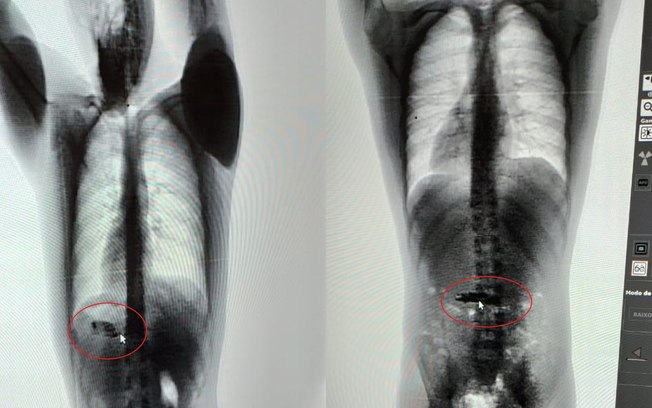

Ele foi alvejado na região lombar e o projétil ficou alojado entre o tórax e a axila

Beatriz foi transferida ao hospital João Paulo II para procedimentos cirúrgico quanto a retirada do projétil alojado na coxa dela